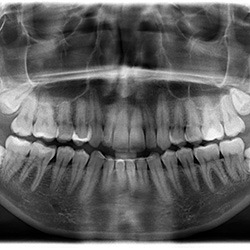

Wisdom teeth are the molars found in the very back of your mouth. They usually appear in the late teens or early twenties but may become impacted (fail to erupt) due to lack of room in the jaw or angle of entry. Most people develop four wisdom teeth, but it is also possible to develop one, two, three, or five or more. Some people never develop any wisdom teeth.

Of course, even if you cannot see your wisdom teeth, that does not mean you do not have them. They might still be beneath your gumline. An X-ray during your next dental checkup can reveal for sure whether you have them.